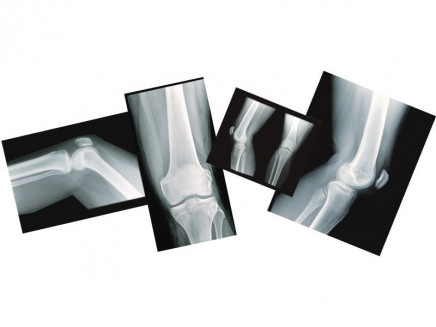

The knee is situated between the two longest bones in the body, the tibia and the femur, commonly referred to as the classic door hinge joint. It is also the largest and heaviest hinge joint present in the body.